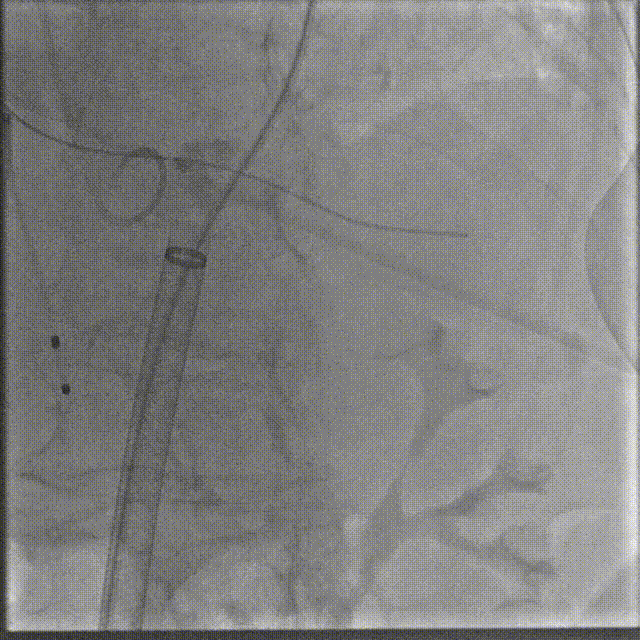

手术过程

根部造影

跨瓣

瓣膜系统过弓

定位造影

瓣膜确认位置后释放

回收极限处造影

最终造影

术后复查造影示瓣膜位置满意,形态良好,冠脉显影良好;TTE示轻微瓣周漏;排除入路血管问题,手术圆满成功。